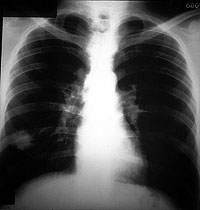

Esquema 22

Comentario placa 22

En la base derecha se observa un nódulo redondeado de 30 mm de diámetro. Sus bordes presentan salientes agudas radiadas o espículas que son más frecuentes en procesos neoplásicos malignos.